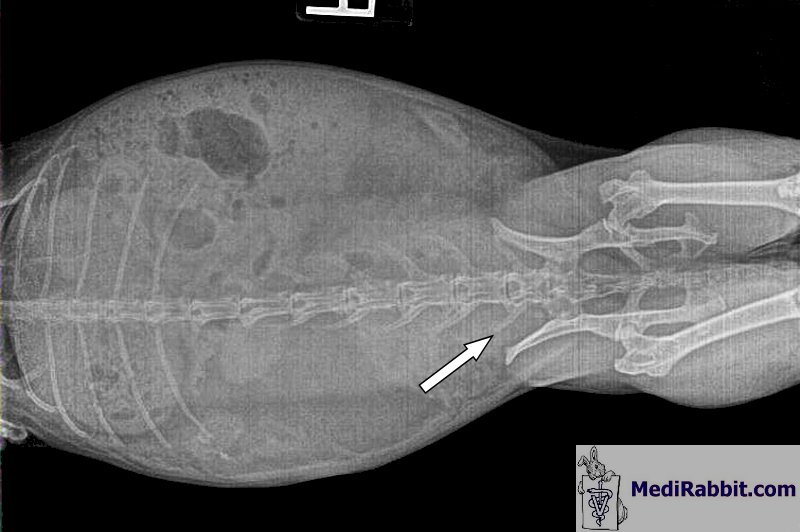

chronique. Scotchie est

un lapin de compagnie âgé de 6 ans. Il souffre de sable urinaire depuis longtemps,

au moins 5 ans et subissait régulièrement des rinçages vésicaux. Ces

radiographies ont été prises quand sa vessie était pleine de ce sable, avant

l’administration de magnésium liquide.